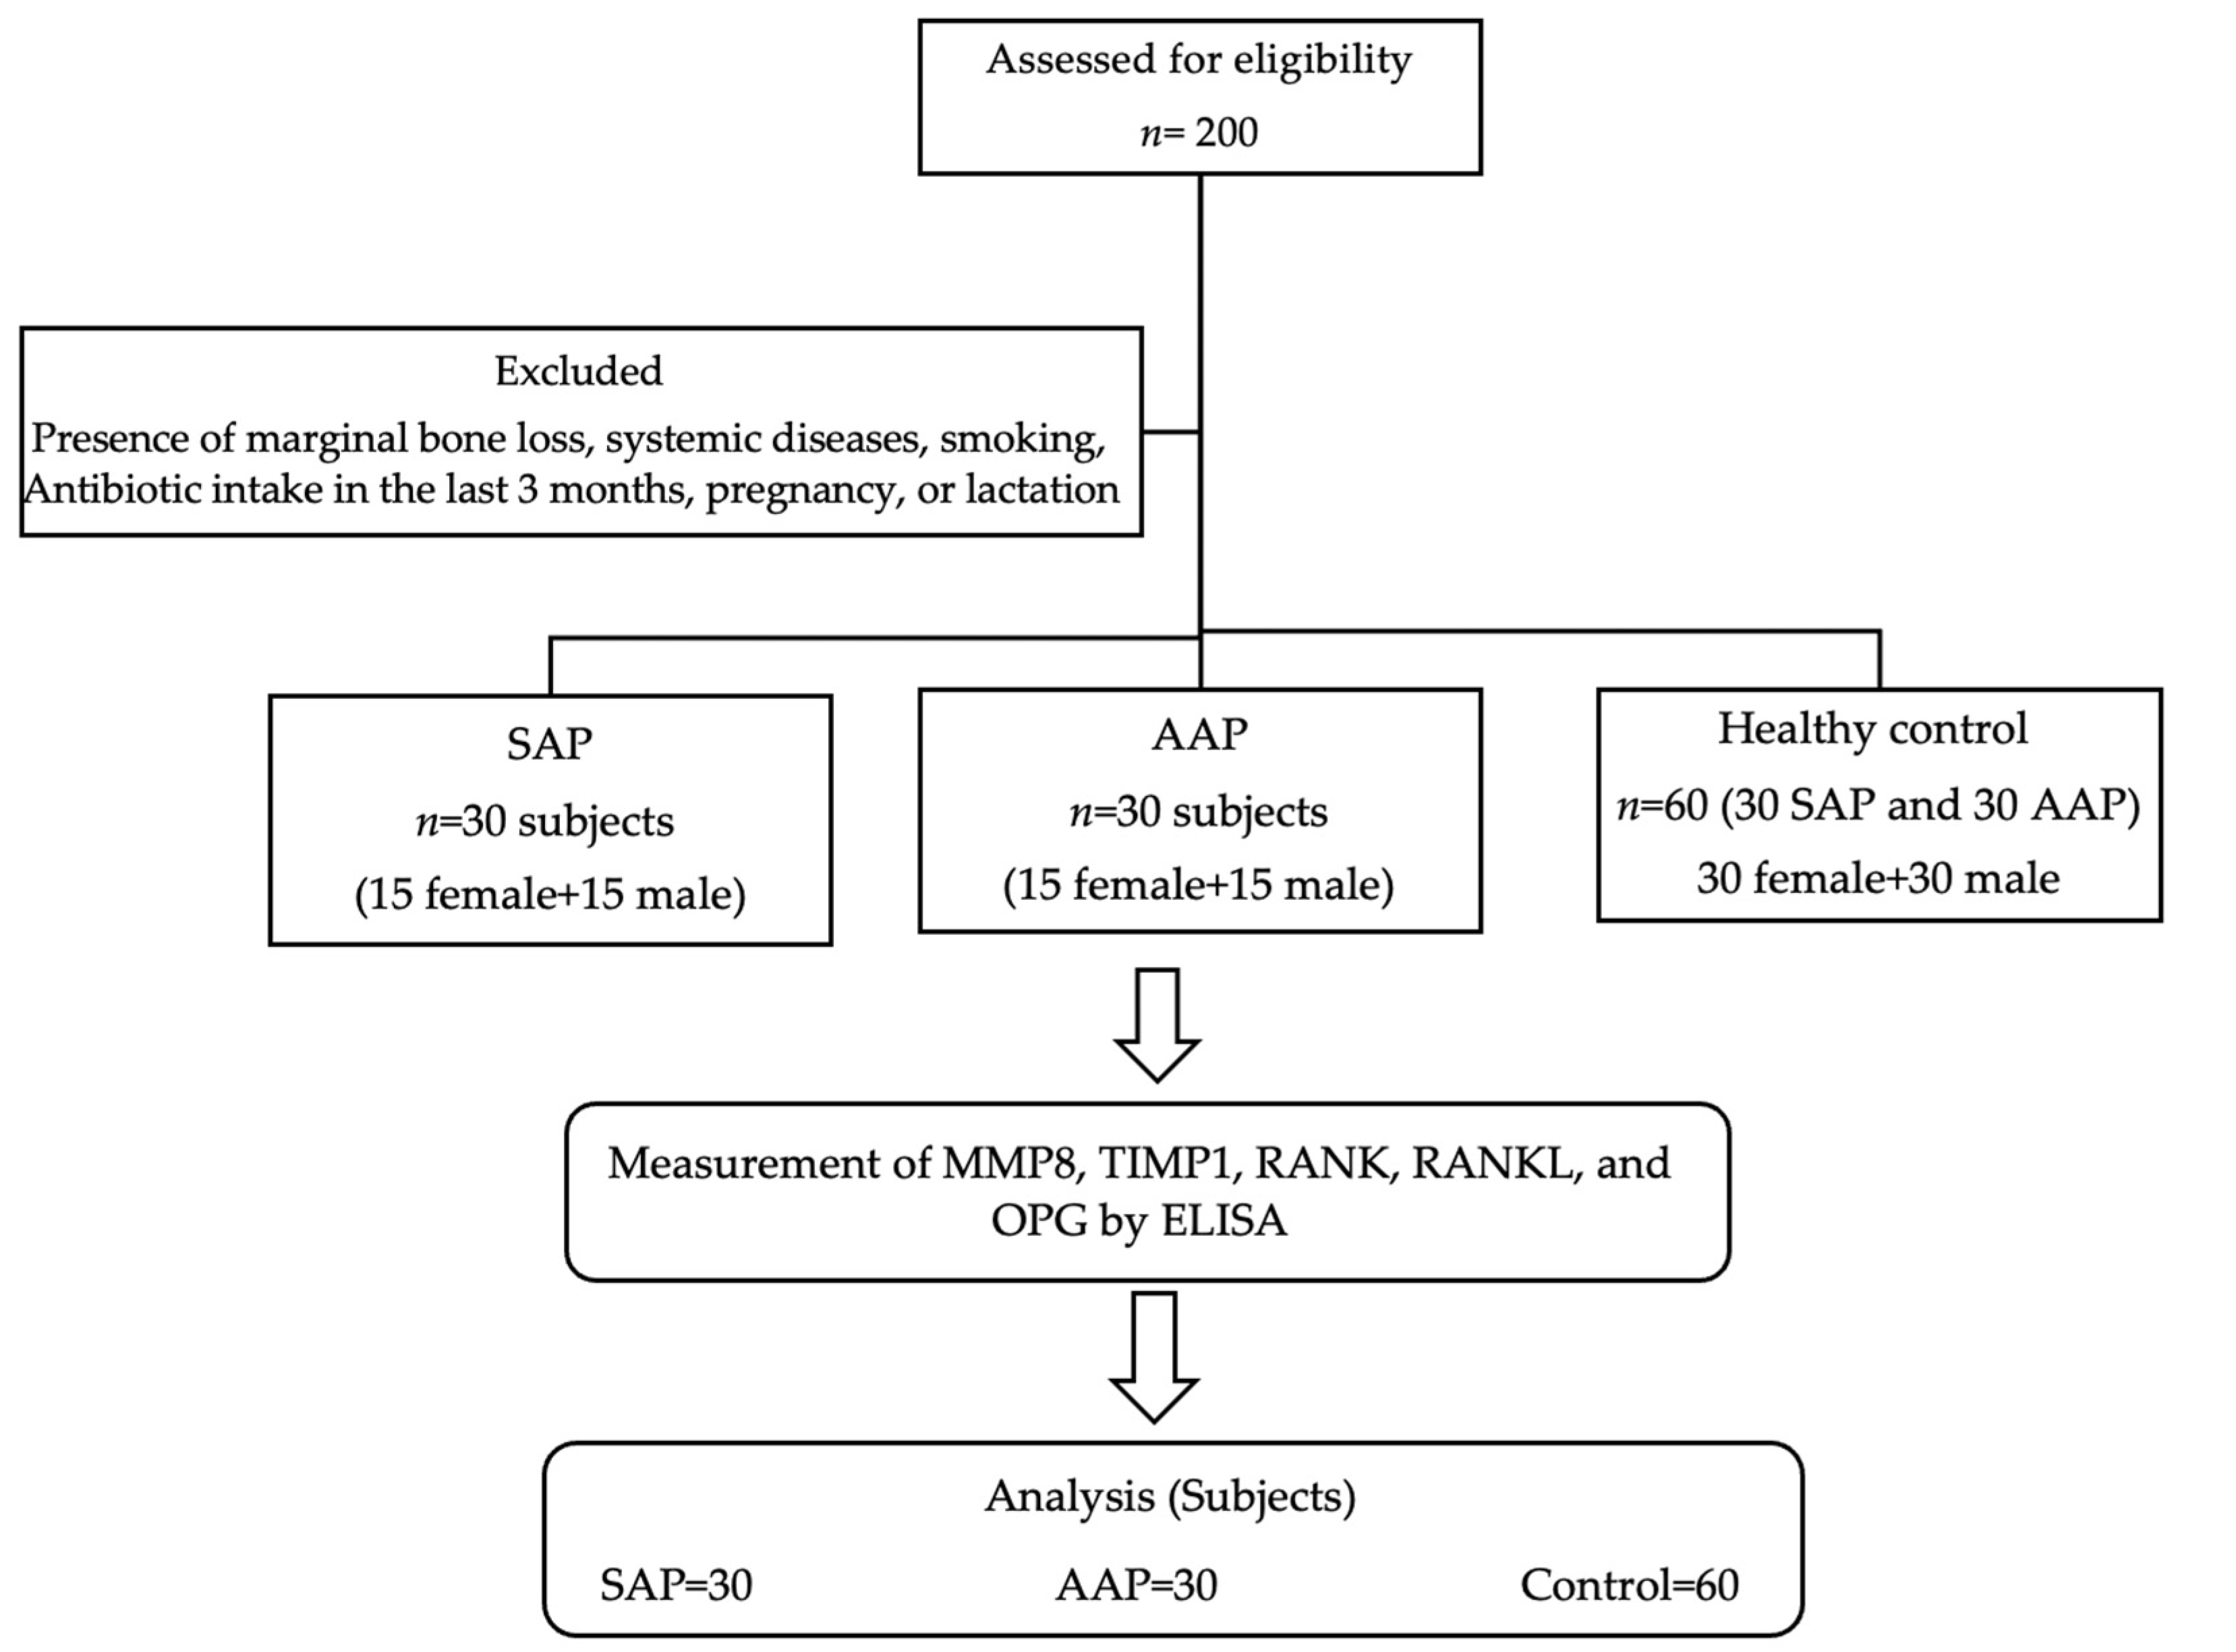

2.1. Study Design

2.2. Study Participants

2.3. Study Criteria

2.5. Pilot Study and Sample Size Calculation